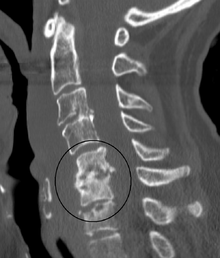

| Discitis in a 2 year old child. | |

Diagnosis is usually apparent on MRI although plain X-rays and CT examinations can be suggestive. The MRI will reveal air changes in the disc and possibly even external involvement involving the bone or epidural regions. A biopsy may be performed and helps with diagnosis in some cases but often an organism is not obtained. C-reactive protein levels and ESR levels will be elevated and are useful for treatment. Often, the white blood cell count will be normal and the patient will be afebrile.